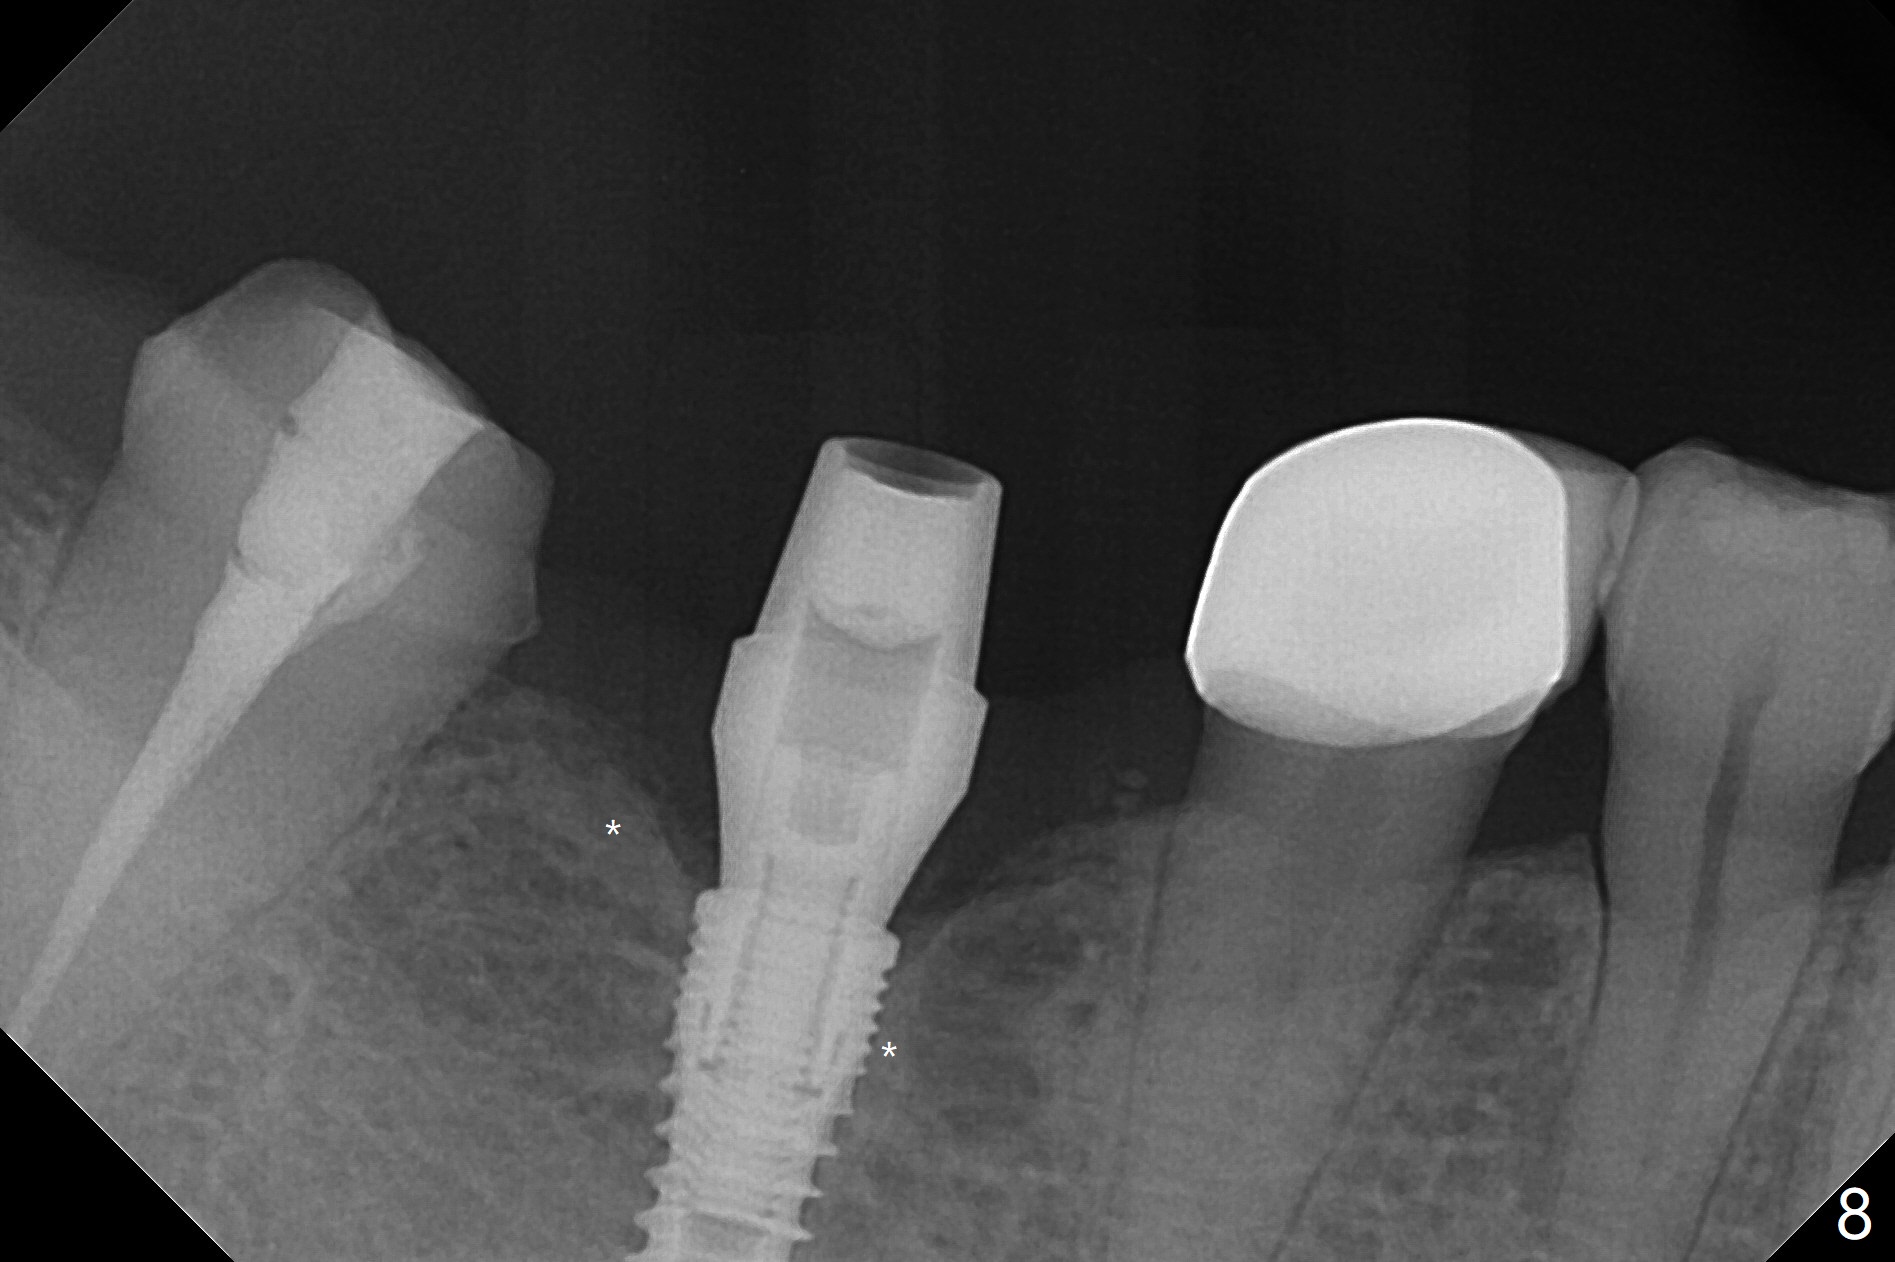

The apparently narrow ridge at #30 before bridge sectioning (Fig.1) is confirmed with incision (Fig.2). Following ridge reduction, osteotomy is initiated with 2 mm pilot drill (Fig.3). When a 3.8x12 mm SM narrow implant is placed with 40 Ncm, there is 1-2 mm cortical bone buccolingually (Fig.4,5). The thick cortices do not seem to be easy to be bent, i.e., expanded. RCT is finished at #31 one month post implant placement (Fig.6,7), the flattened ridge appears to have started to undergo remodeling. Ridge reduction makes it possible for the implant to remain subcrestal postop (Fig.4). The bone surrounding the implant may reduce the likelihood of implant fracture. The crowns at #30 and 31will be fabricated together with light occlusion at #30. In fact the splinted provisional dislodges. There appears dense bone formation 3 months postop (Fig.8 *). The drawback of using a SM narrow implant is that a narrow abutment has to be used (4.8x4(4.5) mm). The implant crown is dislodged immediately after the patient finishes lunch. Following recementation, the occlusion is reduced. In fact, UF or IBS has no such drawback: the implant could be small, but the abutment could be large. One year post cementation, the crown at #31 needs recementation (Fig.9); the bone density next to the coronal implant increases (*).